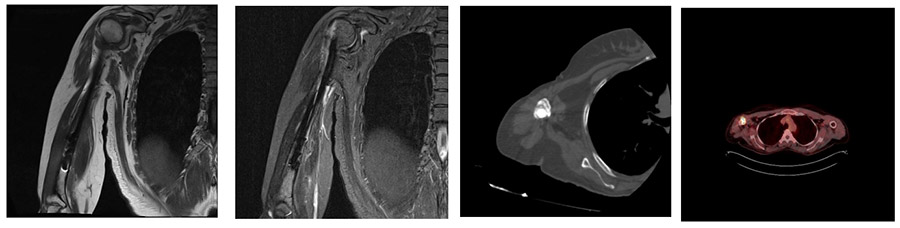

Ameliyat Öncesi: MR’da çivi nedeniyle yoğun artefak, PET_CT’de atmış aktivite görülmekte